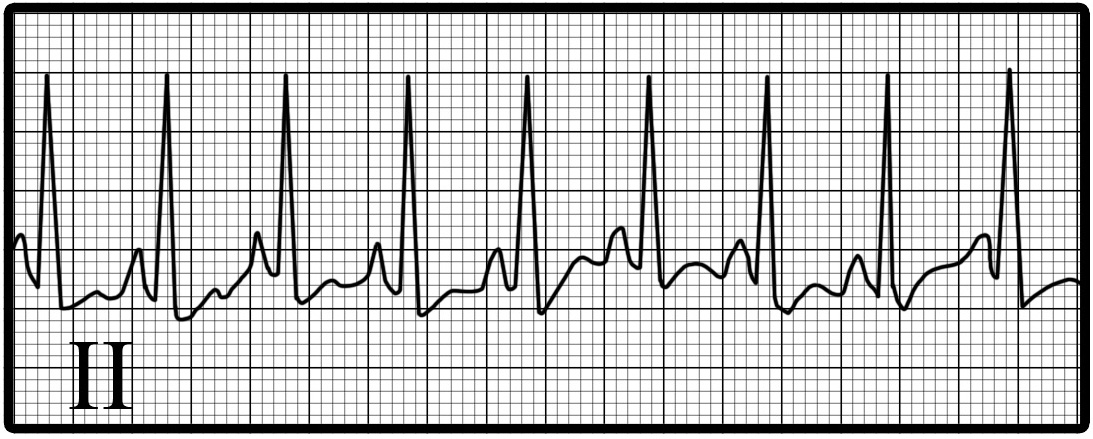

You are incorrect - The best interpretation of the rhythm strip in our patient is atrial fibrillation.

The characteristic features demonstrated here include:

Regular P waves preceding each QRS, with the P waves upright in lead II; a constant P-R interval; and a rate ranging from 100-180 beats per minute.